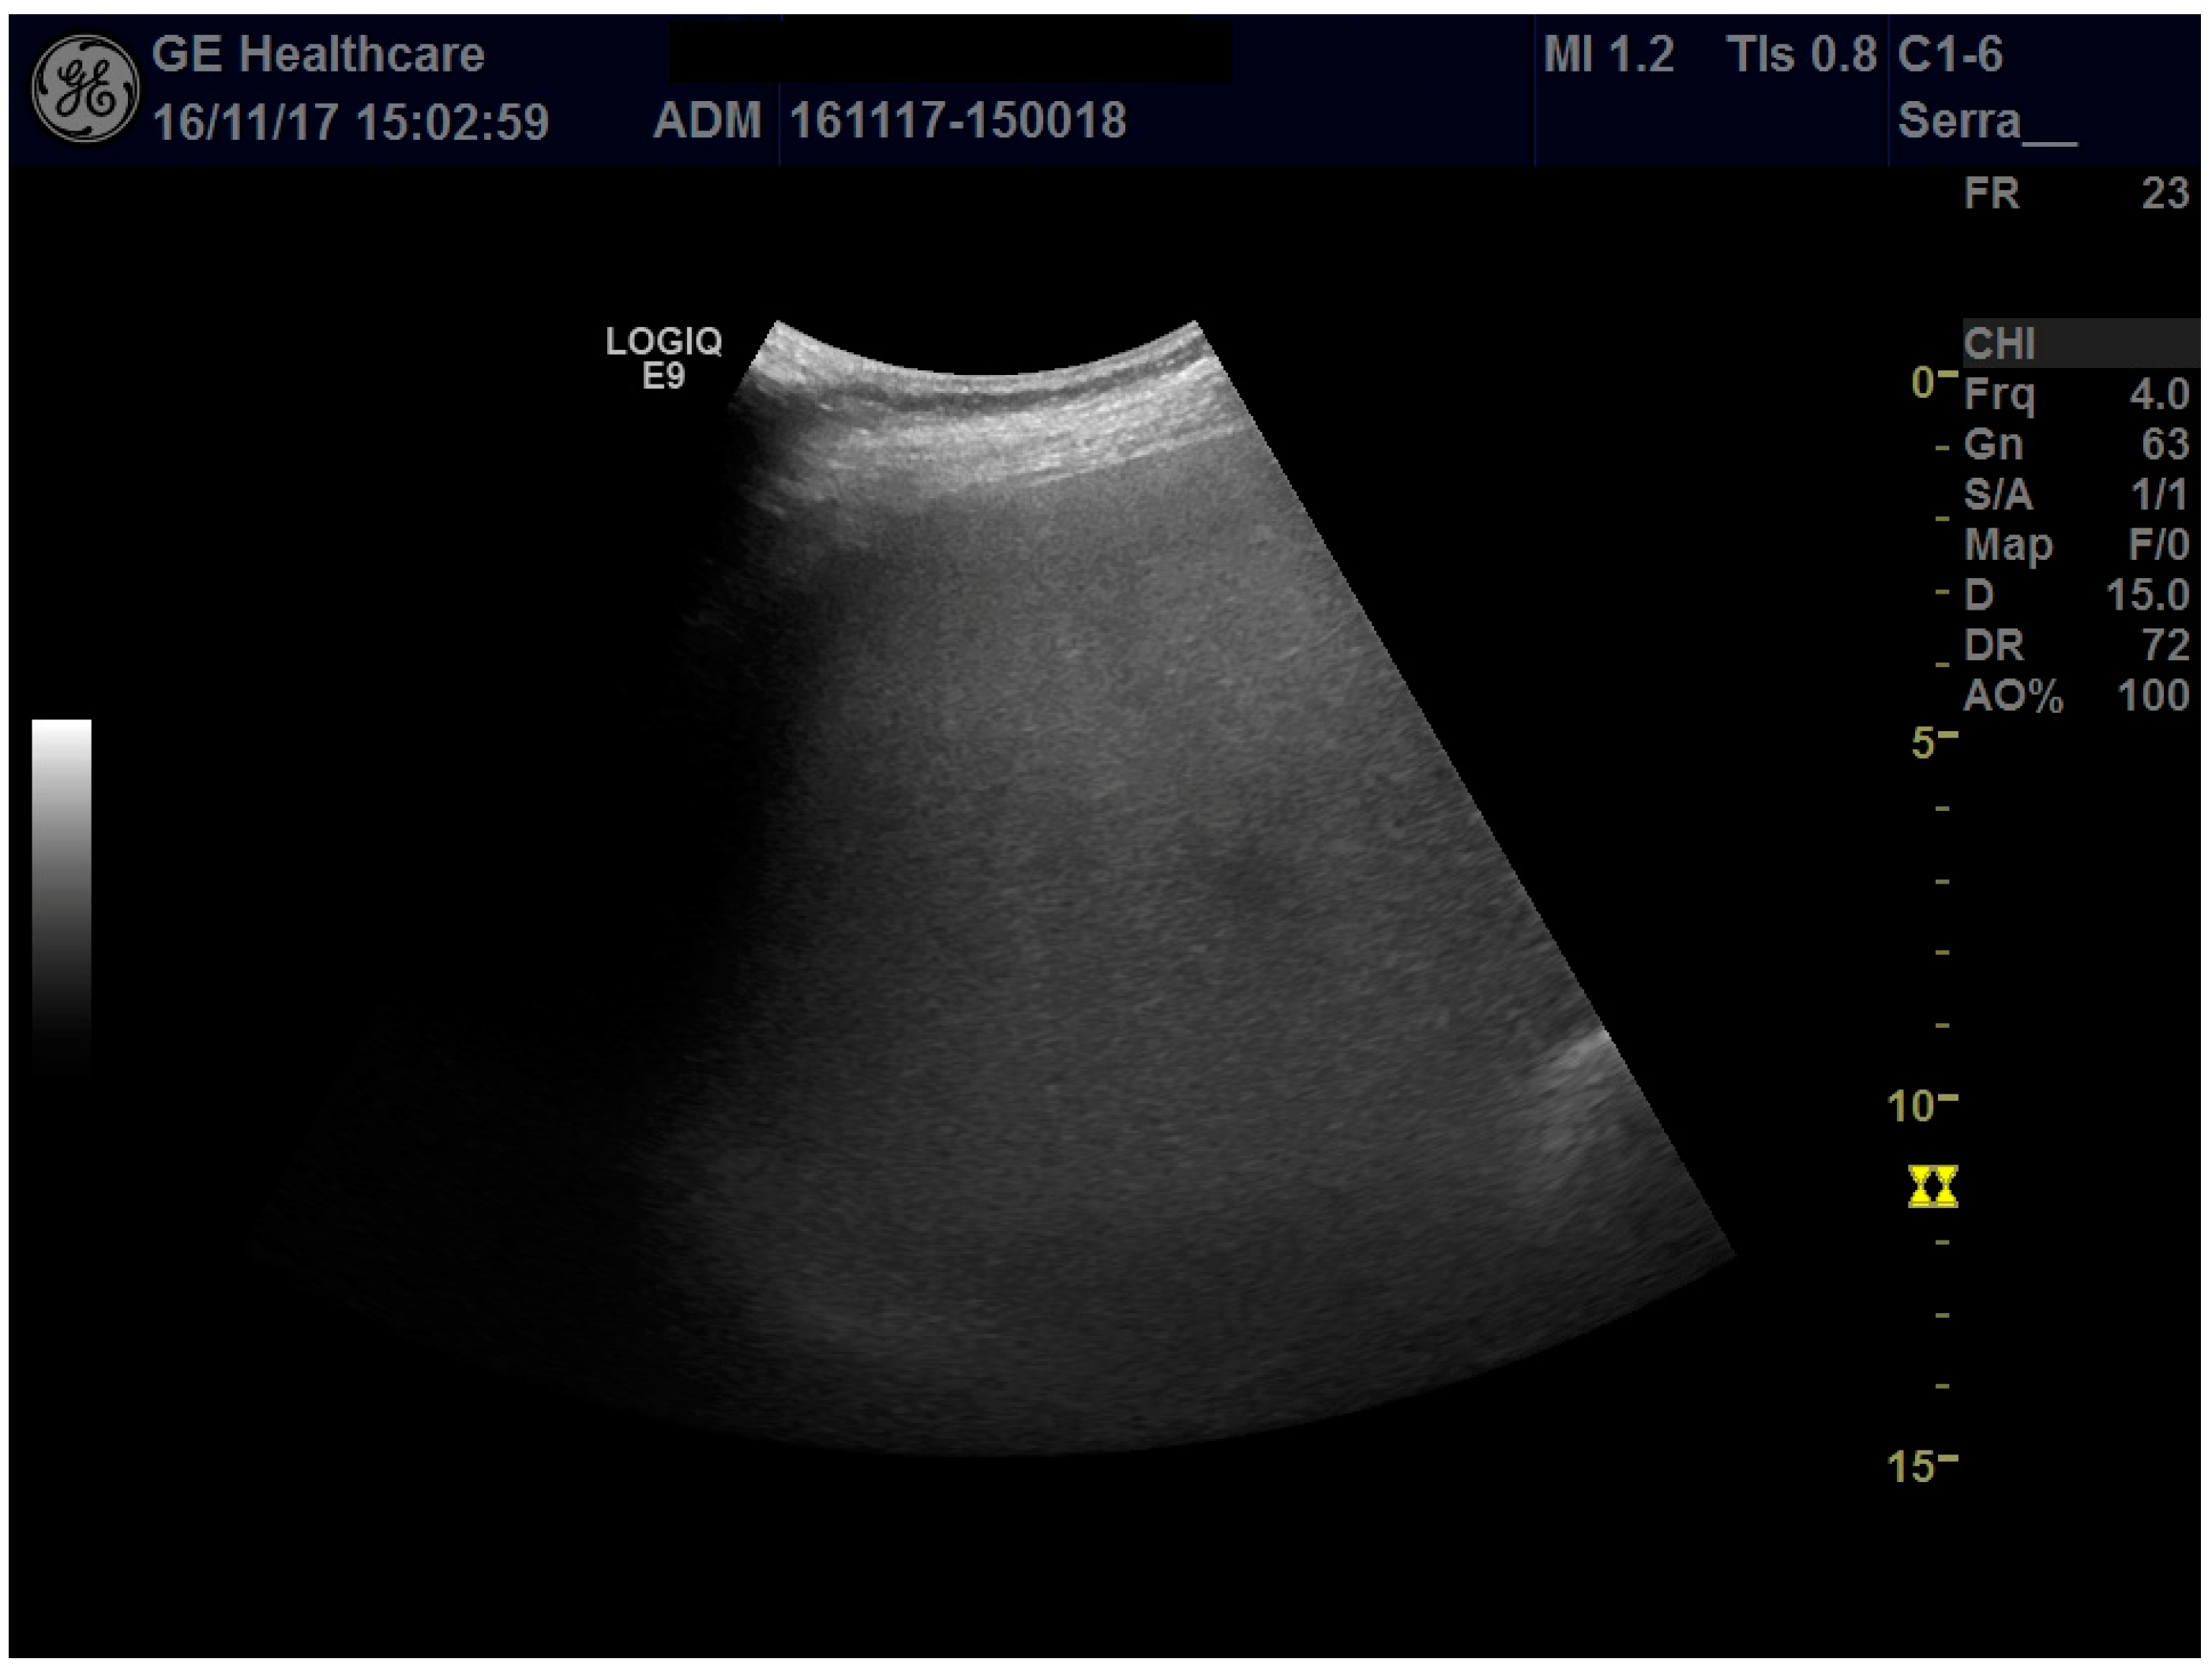

The study conformed to the guidelines outlined by the 1975 Declaration of Helsinki, and written consent was obtained from the patient. A 35-year-old female primigravida at 32 + 3 weeks of a dichorionic diamniotic (DCDA) twin pregnancy from homologous in vitro fertilization (IVF) was admitted to the division of prenatal medicine of Sant’Orsola-Malpighi Hospital. In line with the IVF protocol, the patient received combined estrogen and progesterone supplementation until gestation week 12. The woman had a BMI of 33 kg/m2 at the appearance of the symptoms (having gained 12 kg in weight). At the time of admission, due to the sudden appearance of abdominal pain as well as generalized itching, laboratory tests showed a mild increase in transaminases above the upper limit of normal and elevated serum bile acid concentrations (23 μmol/L), a picture consistent with ICP; therefore, treatment with ursodeoxycholic acid 1500 mg/day was started. Abdominal ultrasonography revealed an enlarged liver (longitudinal right lobe diameter, 20 cm) with regular margins and marked hyperechogenicity determining attenuation of the ultrasound beam in the deeper segments of the liver, suggestive of severe steatosis (Figure 1); due to the ultrasound beam attenuation, the suprahepatic veins were not visible. Liver elastography with 2Dlogic E9 gave a liver stiffness value of 1.48 ± 0.13 m/s.

Figure 1. Ultrasound examination of the right liver lobe: the enlarged liver appears typically as “bright”, with fine, closely packed echoes without visualization of the vessels, as in the case of severe hepatic steatosis.